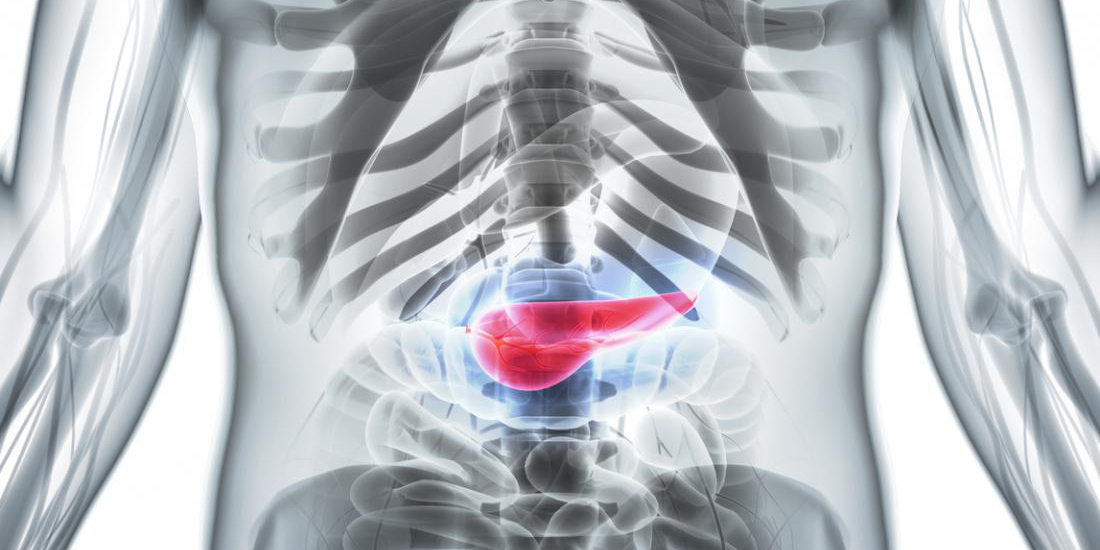

Фотографии медицинских исследований инсулиномы и синдрома Триады Уиппла